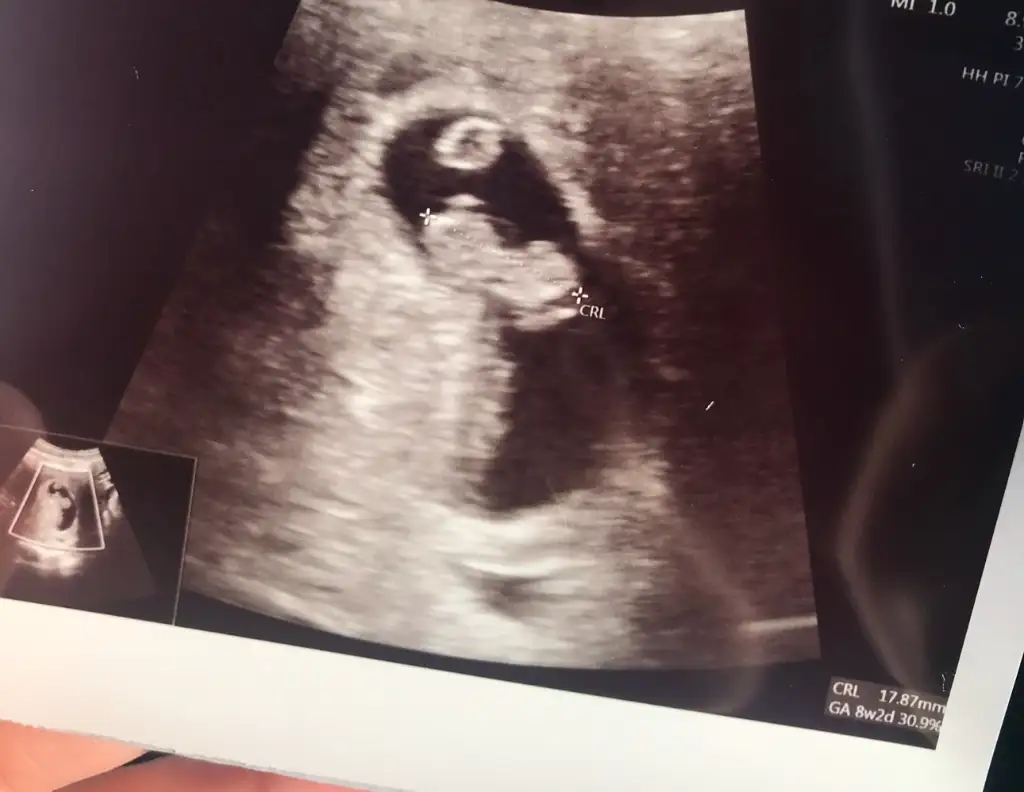

Banada bakarmısınız rica etsem 8 haftalık karından ultroson

Bende erkek hissediyorum hayırlısı olsun bakalım teşekkür ederim cevapladığınız içinPlasentası sol tarafta görünüyor demekki sağda erkek bebeğe benziyorkesesi de erkek bebeğe benziyor öğrenince yazar mısınız ?

Attığınız ultrasonda yolksac denen o kese hiç görünmüyor ama o yüzden plasenta da belli olmuyor yorum yapamayacağımbana da bakabilir misiniz? 6+3 haftalık abdominal